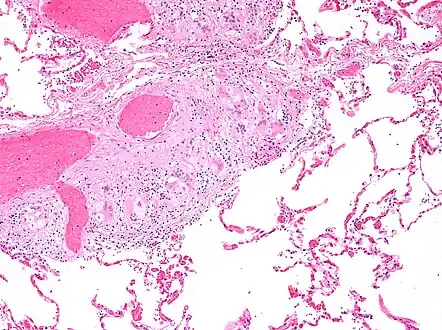

Micrograph of asteroid bodies in pulmonary sarcoidosis. H&E stain.

Micrograph of asteroid bodies in pulmonary sarcoidosis. H&E stain. Micrograph of asteroid bodies in pulmonary sarcoidosis. H&E stain.